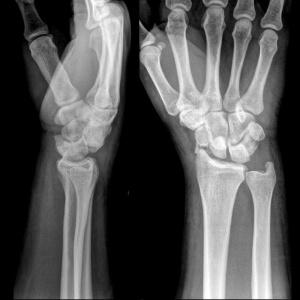

Диагностика

Несмотря на то что первая помощь была оказана успешно, пациенту крайне важно как можно скорее обратиться к травматологу.

Пациенты часто ошибочно принимают травму лучезапястного сустава за вывих или растяжение из-за нечетких симптомов.

Неправильная диагностика может привести к серьезным последствиям в будущем. Поэтому лучше доверить определение диагноза опытному специалисту.

Для точной диагностики недостаточно лишь визуального осмотра травмы, требуется рентгенография. Это позволит врачу детально изучить поврежденный участок и назначить адекватное лечение.

В более сложных случаях может быть полезна компьютерная томография лучезапястного сустава. Серия снимков в разных срезах поможет врачу точно определить характер повреждения.